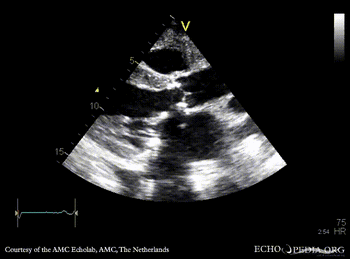

| A3CH: aortic bioprosthesis